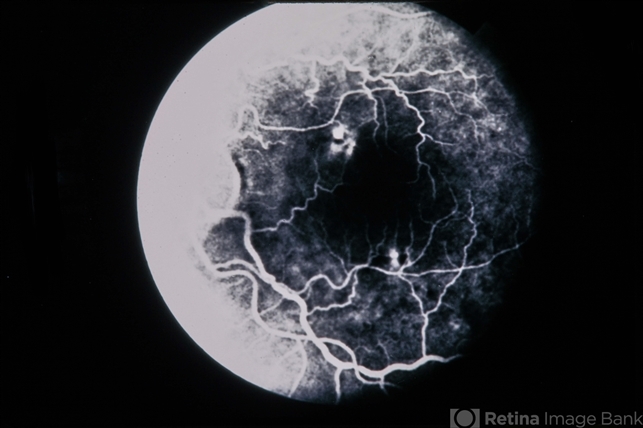

- Combined Retinal RPE Hamartoma

- combined hamartoma, retinal pigment epithelium (RPE) hamartoma

- 66-year-old white female, combined retinal & RPE hamartoma.